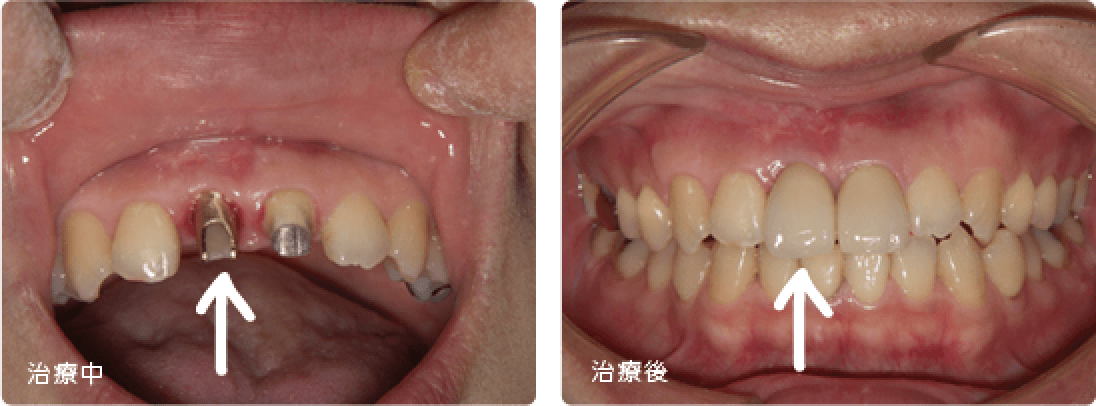

前歯インプラント

臼歯部インプラントは機能優先ですが、前歯部インプラントは機能だけでなく、見た目(審美性)が要求されます。よって抜歯即時埋入(抜歯と同時にインプラントを埋入する方法)や骨移植、歯肉移植など高い技術を伴う治療が必要になる場合があります。